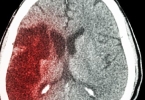

活动性内脏出血或颅内出血病史患者绝对禁止溶栓。近期3周内接受过大手术、分娩或器官活检者,血管创伤风险显著增加。血压超过180/110mmHg时,溶栓可能诱发脑出血。其他相对禁忌证包括严重肝肾功能不全、感染性心内膜炎、糖尿病视网膜病变等出血高风险人群。